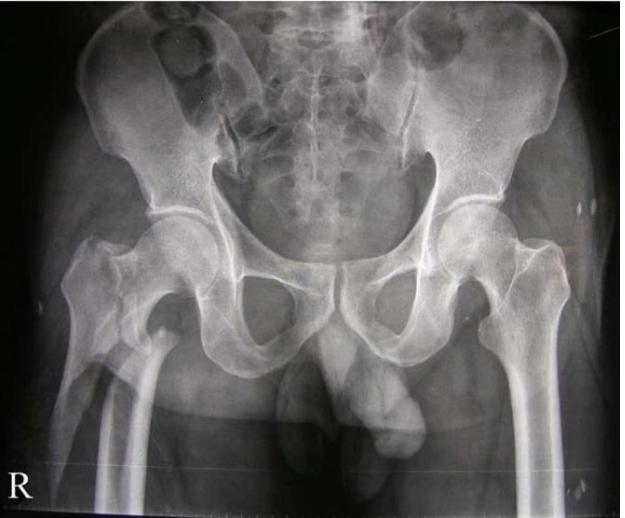

49

abnormalities

**1. galaezzi fracture** 2. radial fracture - transverse, displaced medially and dorsally, shortened, volar angulation 3. distal radial ulna dislocation

diagnosis list imaging and the complication it would search for

right posterior hip dislocation Imaging; CT - acetabular fracture, femoral head fracture MRI - sciatic nerve injury, labral tear

54

what are the four steps in hip reduction

1. sedate 2. stabilise pelvis 3. hip flexed and adducted 4. provide traction | 1.